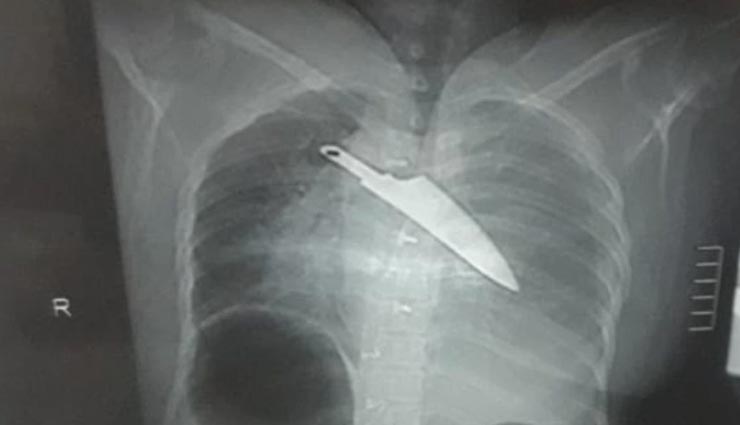

चमत्कार! 30 घंटे तक सीने में चाकू घुसे रहने के बाद भी बच गई महिला की जान